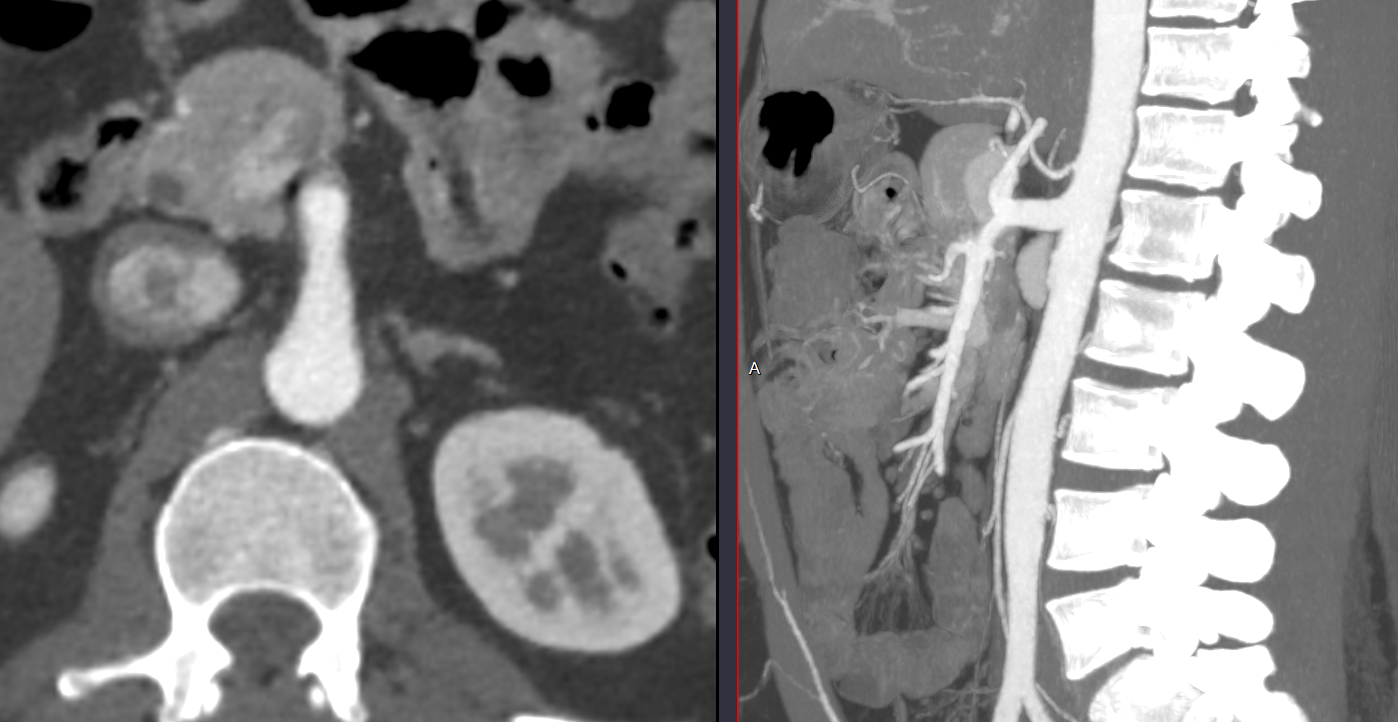

- Origine commune du tronc coeliaque et de l’AMS

- Peuvent faire des Anévrismes